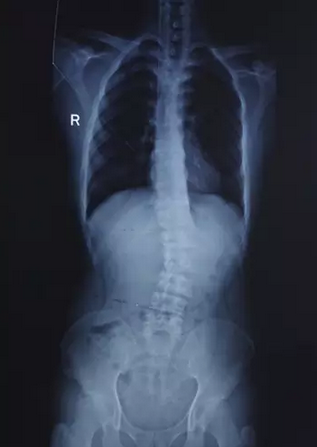

术前照片

2016年3月2日,小张一入院,医务人员在了解他的病情后,随即展开讨论并积极完善相关检查,以明确病因。从各项检查综合分析后,诊断为1、脊柱侧凸 2、腰椎间盘突出症(L3-S1)3、腰椎管狭窄症4、强直性脊柱炎。正常人的脊柱是笔直的,而此时小张的脊柱已类似于“水蛇”状,他的症状相当严重,已影响其生活质量,需尽快手术治疗,以固定、矫正脊柱的形状。